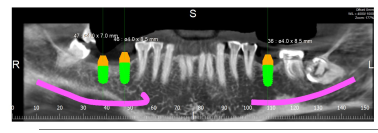

– OPG (DENTAL X-RAY) –

An Orthopantomogram (OPG), also known as an “orthopantogram” or “panorex”, is a panoramic scanning dental X-ray of the upper and lower jaw. It shows a three-dimensional view of a half-circle from ear to ear.